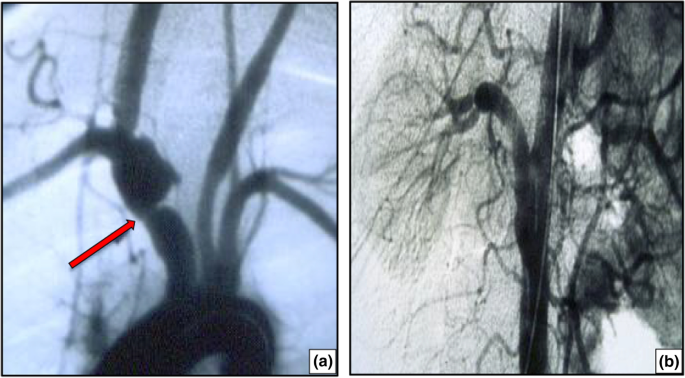

Fig. 3

figure 3

a Stenosis of the anonymous trunk with post-stenotic dilation in a 21-year-old young lady with type I Takayasu arteritis. b A 34-year-old male patient was diagnosed with type V Takayasu arteritis, sub-occlusive stenosis of the right renal artery, and arterial hypertension. Following aorto-renal bypass surgery, blood pressure was normalized and anti-hypertensive medication was no longer required